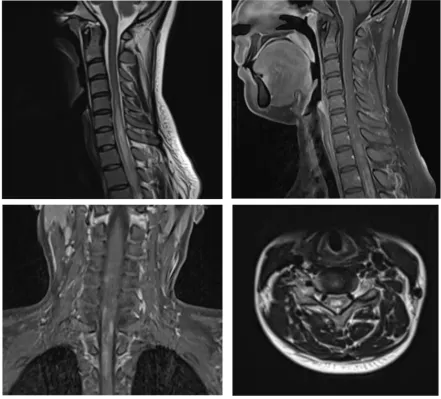

病例一 小崔是一個(gè)身強(qiáng)力壯的大四學(xué)生,即將離開校園步入社會(huì),一天早上起床感覺(jué)頭暈,伴有惡心和嘔吐,自覺(jué)四肢麻木,看東西出現(xiàn)雙影,第二天出現(xiàn)走路不穩(wěn),在家人的陪同下去了當(dāng)?shù)乜h醫(yī)院,診斷“前庭神經(jīng)炎”,輸液治療,癥狀沒(méi)有明顯好轉(zhuǎn)。小崔的母親非常著急,帶著小崔來(lái)到滄州市中心醫(yī)院神經(jīng)免疫、中樞神經(jīng)系統(tǒng)感染二科就診,劉潔瓊主任團(tuán)隊(duì)通過(guò)詳細(xì)地詢問(wèn)病史、查體,對(duì)患者進(jìn)行了腰椎穿刺顯示寡克隆區(qū)帶(+),頭頸胸部增強(qiáng)核磁共振顯示大腦和腦干多發(fā)異常信號(hào),再次追問(wèn)病史,小崔入院前4月余曾有右側(cè)肢體麻木,未予重視,自行好轉(zhuǎn),判斷小崔所患的疾病是復(fù)發(fā)緩解型多發(fā)性硬化,立即給予患者激素沖擊治療,數(shù)天后小崔癥狀完全緩解。為了防止疾病再次復(fù)發(fā)對(duì)小崔日后的生活和工作造成影響,劉潔瓊主任結(jié)合國(guó)際最新研究成果及指南,給予患者生物制劑皮下注射,患者目前無(wú)不良反應(yīng),已經(jīng)進(jìn)入工作崗位開始了新生活。 病例二 張女士?jī)赡昵吧⒆雍蟪霈F(xiàn)右眼視物模糊,就診于當(dāng)?shù)蒯t(yī)院診斷為視神經(jīng)炎,一直服用免疫抑制劑治療。半月前的一天張女士感覺(jué)背部發(fā)麻,以為著涼,未予重視,后來(lái)張女士又出現(xiàn)了雙下肢麻木無(wú)力、走路不穩(wěn),同時(shí)自覺(jué)排尿、排便費(fèi)力,張女士的家人馬上意識(shí)到了問(wèn)題的嚴(yán)重性,趕緊帶著張女士就診于滄州市中心醫(yī)院急診入住脊髓外科?;颊甙Y狀進(jìn)行性加重,起初尚能行走,短短兩天已進(jìn)展至臥床狀態(tài),下肢抬起困難,身體麻木感也發(fā)展到胸部及以下,完善脊髓核磁掃描顯示脊髓長(zhǎng)節(jié)段異常信號(hào)伴腫脹,考慮中樞神經(jīng)系統(tǒng)脫髓鞘病,遂轉(zhuǎn)往醫(yī)院神經(jīng)免疫、中樞神經(jīng)系統(tǒng)感染二科,劉潔瓊主任團(tuán)隊(duì)細(xì)致詢問(wèn)病史、查體,并進(jìn)行腰椎穿刺顯示水通道蛋白4抗體(+),判斷張女士所患疾病為視神經(jīng)脊髓炎譜系疾病,立即給予激素沖擊治療,數(shù)天后張女士的癥狀逐漸恢復(fù)正常。 視神經(jīng)脊髓炎譜系疾病是由水通道蛋白4抗體介導(dǎo)的中樞神經(jīng)系統(tǒng)脫髓鞘疾病,主要表現(xiàn)為反復(fù)發(fā)作的視神經(jīng)炎和橫貫性脊髓炎,90%以上為多時(shí)相病程,其中40-60%在1年內(nèi)復(fù)發(fā),約90%在3年內(nèi)復(fù)發(fā),任何一次臨床發(fā)作均有可能帶來(lái)不可逆性損傷,因此,視神經(jīng)脊髓炎譜系疾病一經(jīng)診斷后應(yīng)盡早開始序貫治療并堅(jiān)持長(zhǎng)程規(guī)律預(yù)防。 病例三 小魏是個(gè)14歲的初中生,一天“感冒”后出現(xiàn)發(fā)熱,體溫在37.5-37.7℃之間,口服退熱藥后堅(jiān)持上學(xué)?!案忻啊眱商旌蟮那宄浚∥撼酝暝顼垳?zhǔn)備去上學(xué),突然出現(xiàn)四肢抽搐伴意識(shí)不清,伴舌咬傷,持續(xù)數(shù)分鐘后抽搐好轉(zhuǎn),但仍意識(shí)模糊,躁動(dòng)不安,這可嚇壞了小魏的父母,趕緊帶著孩子來(lái)到了滄州市中心醫(yī)院神經(jīng)免疫、中樞神經(jīng)系統(tǒng)感染二科,劉潔瓊主任詳細(xì)查看病人后立即進(jìn)行頭顱CT、抽血化驗(yàn)和腰椎穿刺術(shù),腦脊液結(jié)果顯示MOG抗體(+),判斷小魏是MOG抗體相關(guān)性腦炎,經(jīng)過(guò)治療小魏第二日神智轉(zhuǎn)清,半月后好轉(zhuǎn)出院,重歸課堂。 神經(jīng)免疫、中樞神經(jīng)系統(tǒng)感染二科 滄州市中心醫(yī)院神經(jīng)內(nèi)科醫(yī)學(xué)中心神經(jīng)免疫、中樞神經(jīng)系統(tǒng)感染二科是國(guó)家臨床重點(diǎn)??苿?chuàng)建單位、河北省臨床重點(diǎn)建設(shè)??啤嬷菔信R床重點(diǎn)學(xué)科,是中國(guó)罕見病聯(lián)盟腦炎base數(shù)據(jù)庫(kù)成員單位,是國(guó)家區(qū)域醫(yī)療中心河北省神經(jīng)免疫疾病聯(lián)盟成員單位,致力于中樞神經(jīng)系統(tǒng)自身免疫性疾病和感染性疾病的醫(yī)療、教學(xué)、科研、預(yù)防、保健和康復(fù)工作。擁有一支經(jīng)驗(yàn)豐富、技術(shù)精湛、業(yè)務(wù)素質(zhì)過(guò)硬的專業(yè)技術(shù)隊(duì)伍,現(xiàn)有碩士生導(dǎo)師1名,主任醫(yī)師1名、副主任醫(yī)師1名、主治醫(yī)師2名,博士研究生1名,碩士研究生4名。科室立足國(guó)際視野,為神經(jīng)免疫和中樞神經(jīng)系統(tǒng)感染性疾病患者提供最先進(jìn)的診療理念。科室病房在十樓東區(qū),門診在腦科醫(yī)院二樓2診室,劉潔瓊主任每周二、四出診,黃秋海主任每周六、日出診。科室全體醫(yī)護(hù)人員將銳意進(jìn)取、奮楫篤行,用精湛醫(yī)術(shù)和人文關(guān)懷為廣大患者提供一流的服務(wù)。 科室診療范圍: 1.以臨床孤立綜合癥、多發(fā)性硬化、脊髓炎、視神經(jīng)脊髓炎譜系疾病、急性播散性腦脊髓炎、同心圓硬化、瘤樣炎性脫髓鞘病等為代表的中樞神經(jīng)系統(tǒng)炎性脫髓鞘性疾病。 2.腦橋中央髓鞘溶解癥、腦橋外髓鞘溶解癥、腦白質(zhì)營(yíng)養(yǎng)不良。 3.各種感染性腦炎、腦膜炎,包括病毒性腦炎/腦膜炎,化膿性腦膜炎、結(jié)核性腦膜炎、真菌性腦膜炎、朊蛋白病、腦囊蟲病、神經(jīng)梅毒等。 4.自身免疫性腦炎和小腦炎,包括抗NMDA受體抗體、抗LG1抗體、抗GABA受體抗體等腦炎。 5.中樞神經(jīng)系統(tǒng)血管炎 6.重癥肌無(wú)力 7.神經(jīng)系統(tǒng)副腫瘤綜合癥 8.其他中樞神經(jīng)系統(tǒng)與自身免疫相關(guān)的疾病和疑難雜癥 科室特色技術(shù)項(xiàng)目: 1、神經(jīng)免疫亞專業(yè):為神經(jīng)系統(tǒng)免疫性疾病患者提供全面?zhèn)€體化的治療方案,包括急性期激素沖擊、血漿置換、免疫吸附、丙種球蛋白治療和緩解期的免疫抑制治療,以及多發(fā)性硬化的免疫修正治療,與胸外科合作進(jìn)行重癥肌無(wú)力患者經(jīng)胸腔鏡微創(chuàng)胸腺摘除術(shù),與神經(jīng)外科合作為疑難患者開展立體定向腦活檢手術(shù)。 2、中樞神經(jīng)系統(tǒng)感染亞專業(yè):開展腦脊液細(xì)胞學(xué)、病原微生物二代測(cè)序技術(shù)為中樞神經(jīng)系統(tǒng)感染患者提供精準(zhǔn)的診斷和治療??剖覟榛颊呓n案,開設(shè)專病隨訪門診,定期進(jìn)行臨床和影像學(xué)的隨訪。建立微信平臺(tái),為患者提供專業(yè)的健康指導(dǎo)和便捷的隨訪路徑。 劉潔瓊 滄州市中心醫(yī)院神經(jīng)免疫、中樞神經(jīng)系統(tǒng)感染二科副主任(主持工作),醫(yī)學(xué)博士,副主任醫(yī)師,碩士生導(dǎo)師,河北醫(yī)科大學(xué)學(xué)報(bào)審稿專家,醫(yī)學(xué)參考報(bào)通訊編委,北京大學(xué)訪問(wèn)學(xué)者。中國(guó)研究型醫(yī)院學(xué)會(huì)頭痛與感覺(jué)障礙專業(yè)委員會(huì)委員,北京神經(jīng)內(nèi)科學(xué)會(huì)(BNA)神經(jīng)感染與免疫專委會(huì)委員,河北省醫(yī)學(xué)會(huì)神經(jīng)病學(xué)分會(huì)頭面痛學(xué)組委員,滄州市女醫(yī)師協(xié)會(huì)神經(jīng)內(nèi)科專業(yè)委員會(huì)常務(wù)委員兼秘書。獲河北醫(yī)學(xué)科技獎(jiǎng)一等獎(jiǎng)一項(xiàng),二等獎(jiǎng)一項(xiàng),滄州市科技進(jìn)步獎(jiǎng)三等獎(jiǎng)一項(xiàng),發(fā)表SCI論文和國(guó)內(nèi)核心期刊論文二十余篇。擅長(zhǎng)多發(fā)性硬化、視神經(jīng)脊髓炎譜系疾病、重癥肌無(wú)力、自身免疫性腦炎、各種腦炎和腦膜炎、中樞神經(jīng)系統(tǒng)血管炎、脊髓病變及各種中樞神經(jīng)系統(tǒng)疑難雜癥的診治。